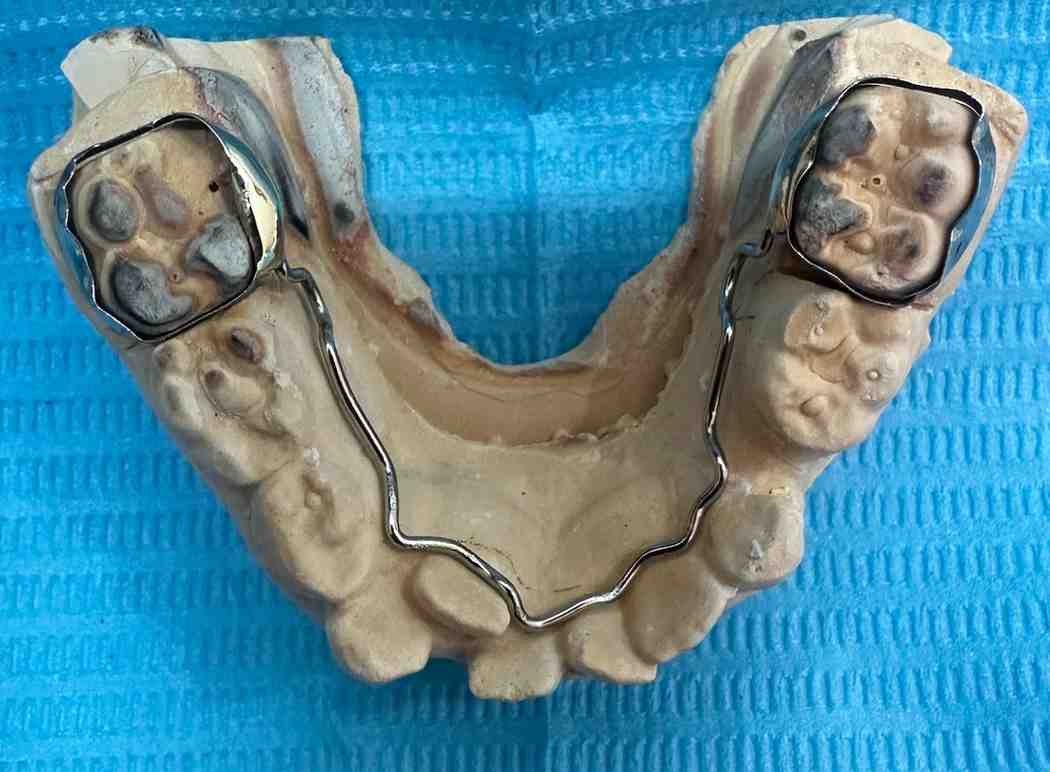

Doctor Pooja recommended that parents have a fixed lingual holding arch and U-loops to maintain dental arch space. The appliance was placed in one appointment, resulting in effective space maintenance and a positive treatment experience.

The diagnosis was accurate due to clinical and radiographic examination, & the lower primary molar is prematurely exfoliating. The clinical examination reveals that adjacent teeth have begun to fill the gap. An X-ray deprived of visible space and a 5-year loss potential revealed emerging permanent tooth buds in anticipated sites. Dr. Pooja was treated using a designed lingual holding arch with U-loops. The device helps to stabilize the molars to allow the adjustment to various mandible development. The parents were thoroughly informed about the process, benefits, and care needs were clarified.

Magnification tools were used to guarantee precise positioning. The U-loops were built into the arch to increase in size as the child develops. The whole process was effective and aimed at reducing the chair-time as much as possible and maximizing the comfort as much as possible.